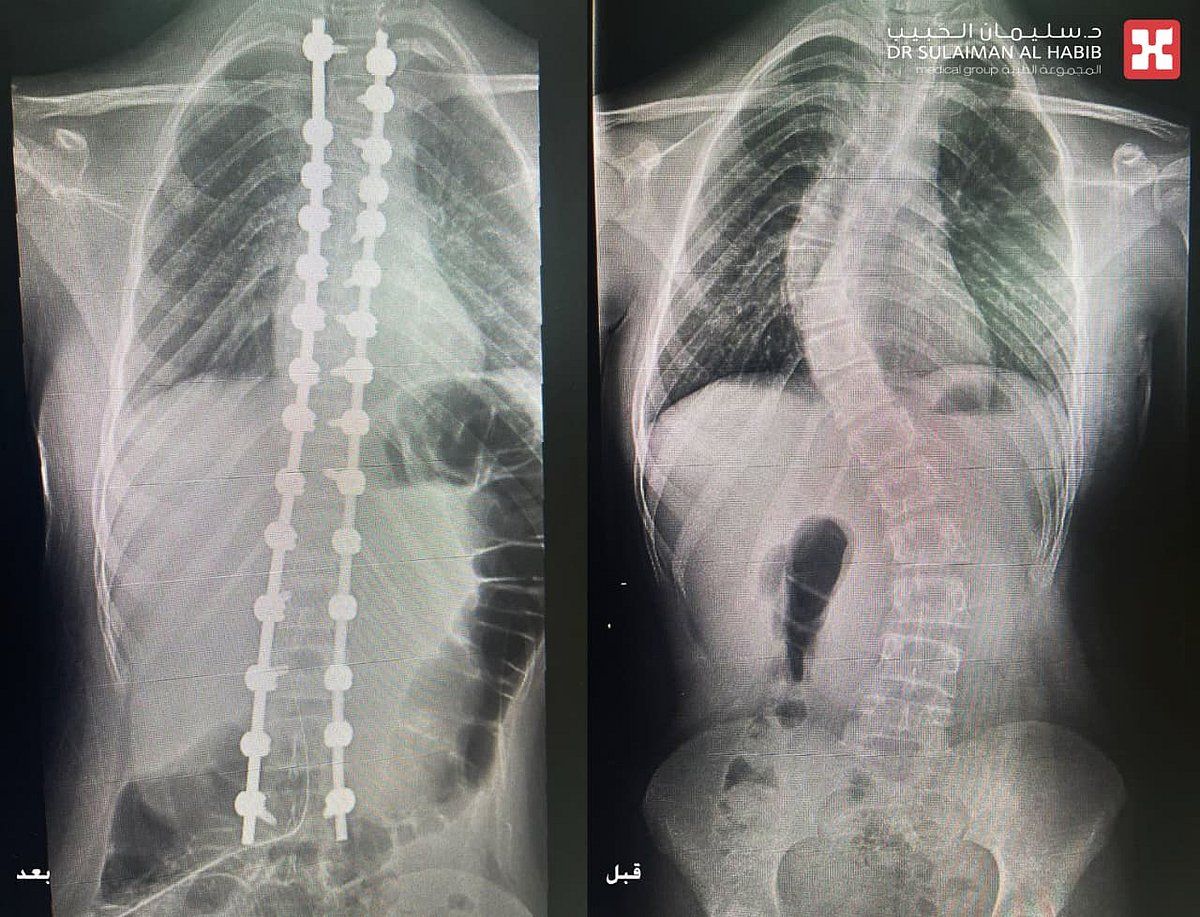

أجرى مجمع الدكتور سليمان الحبيب الطبي بالعليا، عملية جراحية دقيقة لإنهاء معاناة فتاة تبلغ من العمر 13 عاماً، تعاني من إنحناء وجنف مضاعف بالعمود الفقري تبلغ زاويته 70 و45 درجة على التوالي، وذلك عن طريق استخدام تقنيات الذكاء الاصطناعي (AI) والطباعة ثلاثية الأبعاد (3D). ذكر ذلك الدكتور عوض العوض استشاري جراحة العظام والعمود الفقري، رئيس الفريق الطبي المعالج الحاصل على الزمالة الأمريكية والسويدية.

مفيداً بأنه تم اخضاعها لعدد من الفحوصات الطبية الدقيقة بالتصوير المقطعي (C.T Scan)، والأشعة السينية الرقمية (Digital X-Rays)، والرنين المغناطيسي (M.R.I) والتحاليل المخبرية، والتي كشفت بدقة أن الفتاة تعاني من جنف مُضاعف في منطقة فقرات الصدر والفقرات القطنية بزاوية انحراف كبيرة، فضلاً عن وجود إنحراف تعويضي في منطقة التقاء الفقرات الصدرية مع العنقية بنسبة 30 درجة. مشيراً إلى أن هذا النوع من الإعوجاج يُعد من حالات الجنف شديدة التعقيد.

وقد استغرقت العملية قرابة الثلاث ساعات تحت التخدير العام، وتم فيها تعديل فقرات العمود الفقري بدقة عالية، نقلت بعدها المراجعة إلى جناح التنويم، مشيراً إلى أن نتائج الفحوصات ما بعد التدخل الجراحي أكدت نجاح العملية ولله الحمد. وقد بدأت المراجعة في المشي صباح اليوم التالي للعملية، وظهر بوضوح إعتدال العمود الفقري واتزان الأكتاف، وخرجت الفتاة من المستشفى بعد 3 أيام وهي بصحة جيدة .